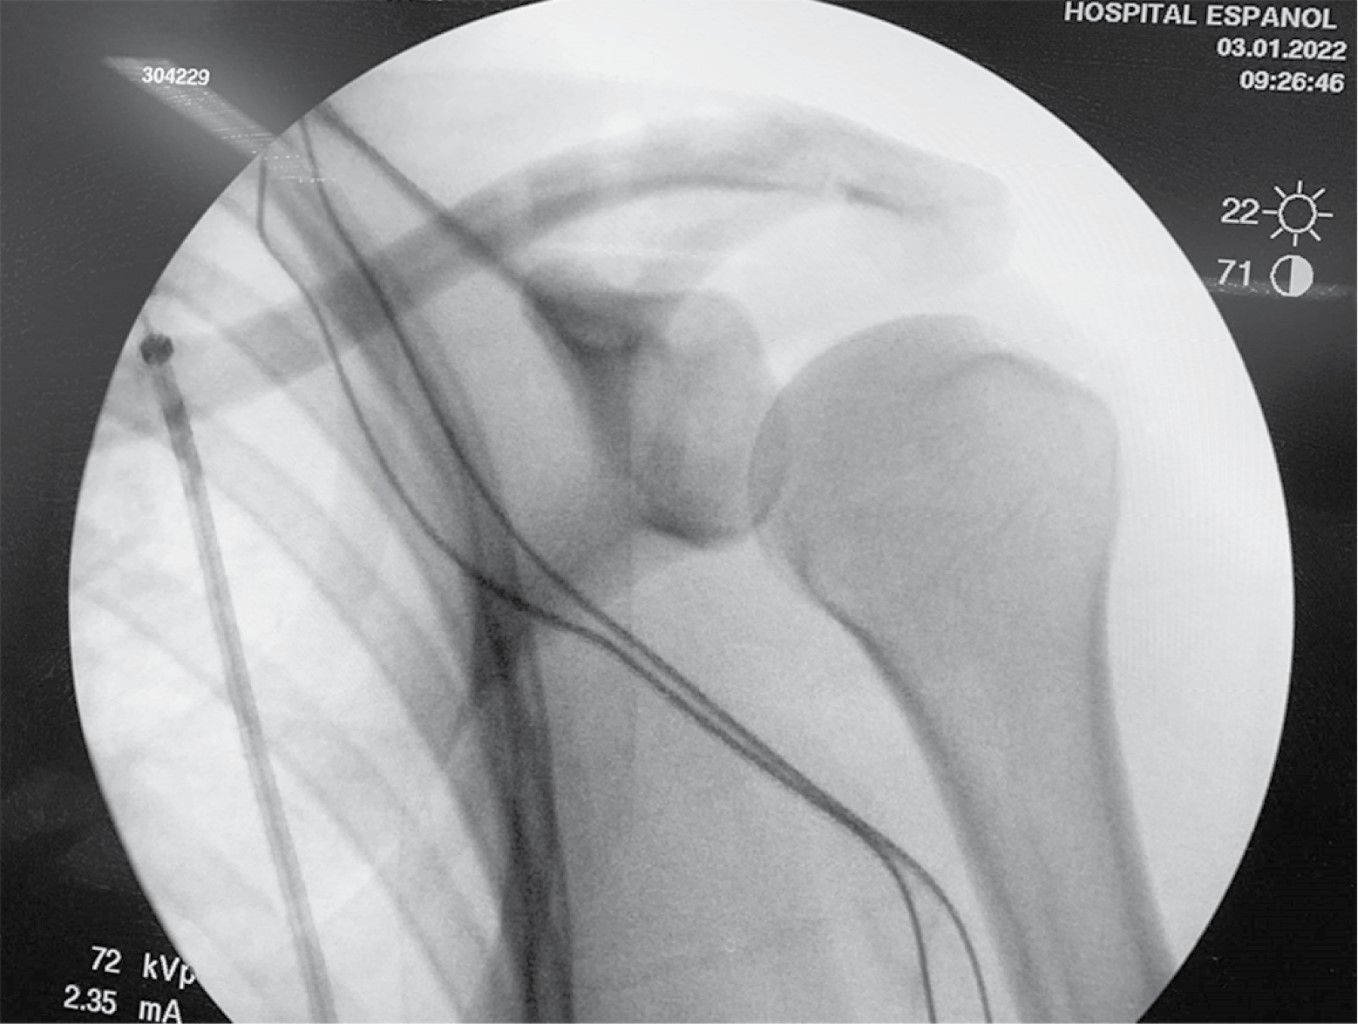

El injerto además de servir para la reconstrucción de los ligamentos CC, su interposición en el espacio AC funciona como espaciador, reemplazando la función del disco articular de dicha articulación. Se toma un control fluoroscópico en proyección anteroposterior, corroborando adecuada reducción de articulación AC (Figura 10). Se procede a irrigar herida quirúrgica con Microdacyn. Se cierra cuidadosamente la fascia deltotrapezoidea con puntos interrumpidos con sutura absorbible (Vicryl 2.0) y posteriormente por planos: tejido celular subcutáneo con sutura Vicryl 2.0 con puntos invertidos en "U" y piel con sutura Stratafix 3-0 con puntos continuos subdérmicos. Se inmoviliza extremidad torácica con inmovilizador de hombro y banda aductora.

Figura 10